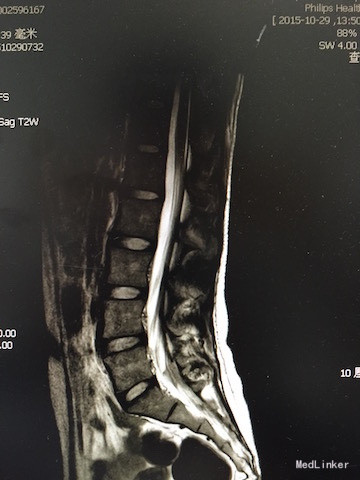

查体:四肢感觉、肌力及肌张力无明显异常,直腿高抬试验(-),双侧足背动脉搏动良好,腰椎活动可,病理征(-)。 辅助检查:胸腰椎MRI(如下图):脊髓下段受牵拉平对第3腰椎下缘,合并脊柱旁占位及脊柱裂可能。

诊断:脊髓栓系综合征 治疗:脊髓栓系松解术

随访与讨论:手术顺利,术后神经受牵拉症状需至少半年才能恢复。诊断及鉴别诊断:脊髓栓系综合征:是由多种脊髓先天性发育异常导致的系列临床综合征。脊髓下段因各种原因受制于椎管终末端,使其位置低于正常。根据该患者临床表现及影像学检查,考虑可能性大。马尾综合征:大多是由于各种先天性或后性原因之腰椎管绝对或相对狭窄,压迫马尾神经而产生一系列神经功能障碍,可有会阴区感染异常及大小便失禁,根据该患者影像学检查。